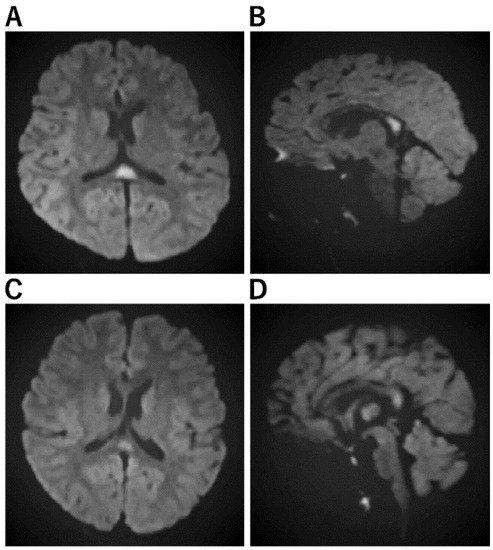

Figure 1. Imaging Characteristics of MERS. (A,B): A Horizontal/B sagittal section was performed on an 8-year-old boy who had an MRI on the third day of fever due to impaired consciousness and unable to recognize his own name. DWI showed an abnormal high signal in the cerebral corpus callosum: WBC 24800, CRP 7.84, Na 133, CL 95, ferritin 119.9, IL-6 171 EEG showed high amplitude slow waves in the occipital region. After 3 days of steroid pulse therapy, the fever resolved and consciousness improved. No sequelae. No causative organism or virus could be identified. (C,D): On the third day of vomiting and fever, he was hospitalized because he could no longer talk to his mother and could not look at her. He had diarrhea and was positive for rotavirus antigen in stool. In the bilateral frontal and occipital regions, EEG revealed persistent high amplitude slow waves. He was diagnosed with MERS on the fifth day after a diffusion-weighted MRI revealed an abnormally high signal in the corpus callosum. mPSL steroid pulse therapy was administered for three days, his level of consciousness improved, and both EEG and MRI were normalized.